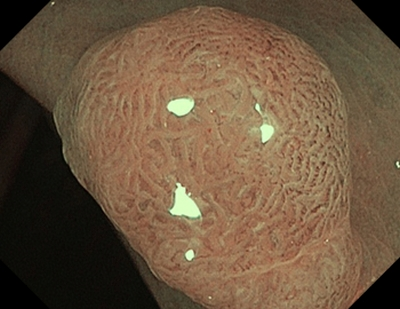

2 тип — характерний для аденоми

Колір: темніший (коричневіший), ніж навколишні

Судини: світліша ділянка в центрі, оточена більш товстими коричневими судинами

Поверхня: овальна, трубчаста, звивиста — наявність трубочок, лінійних або пучкових, світла ділянка в центрі, оточена коричневими судинами